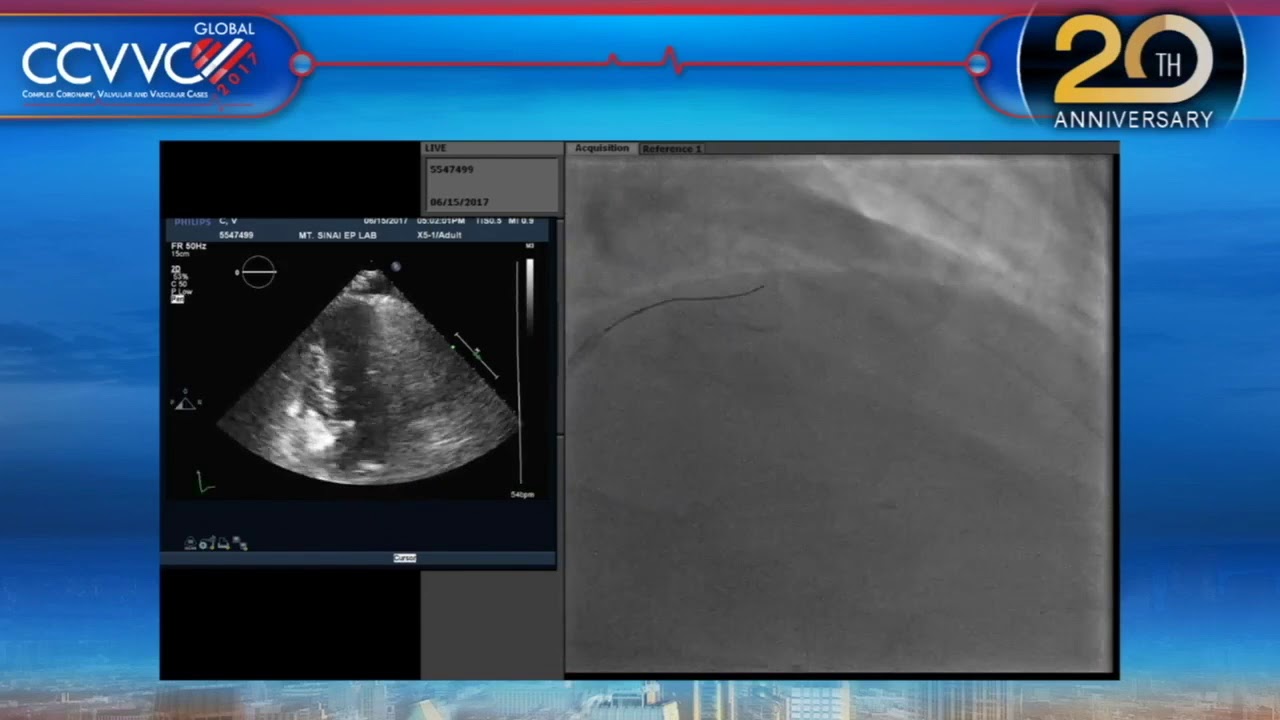

Live Case 14 - Alcohol Septal Ablation under Echo Guidance - CCVVC 2017